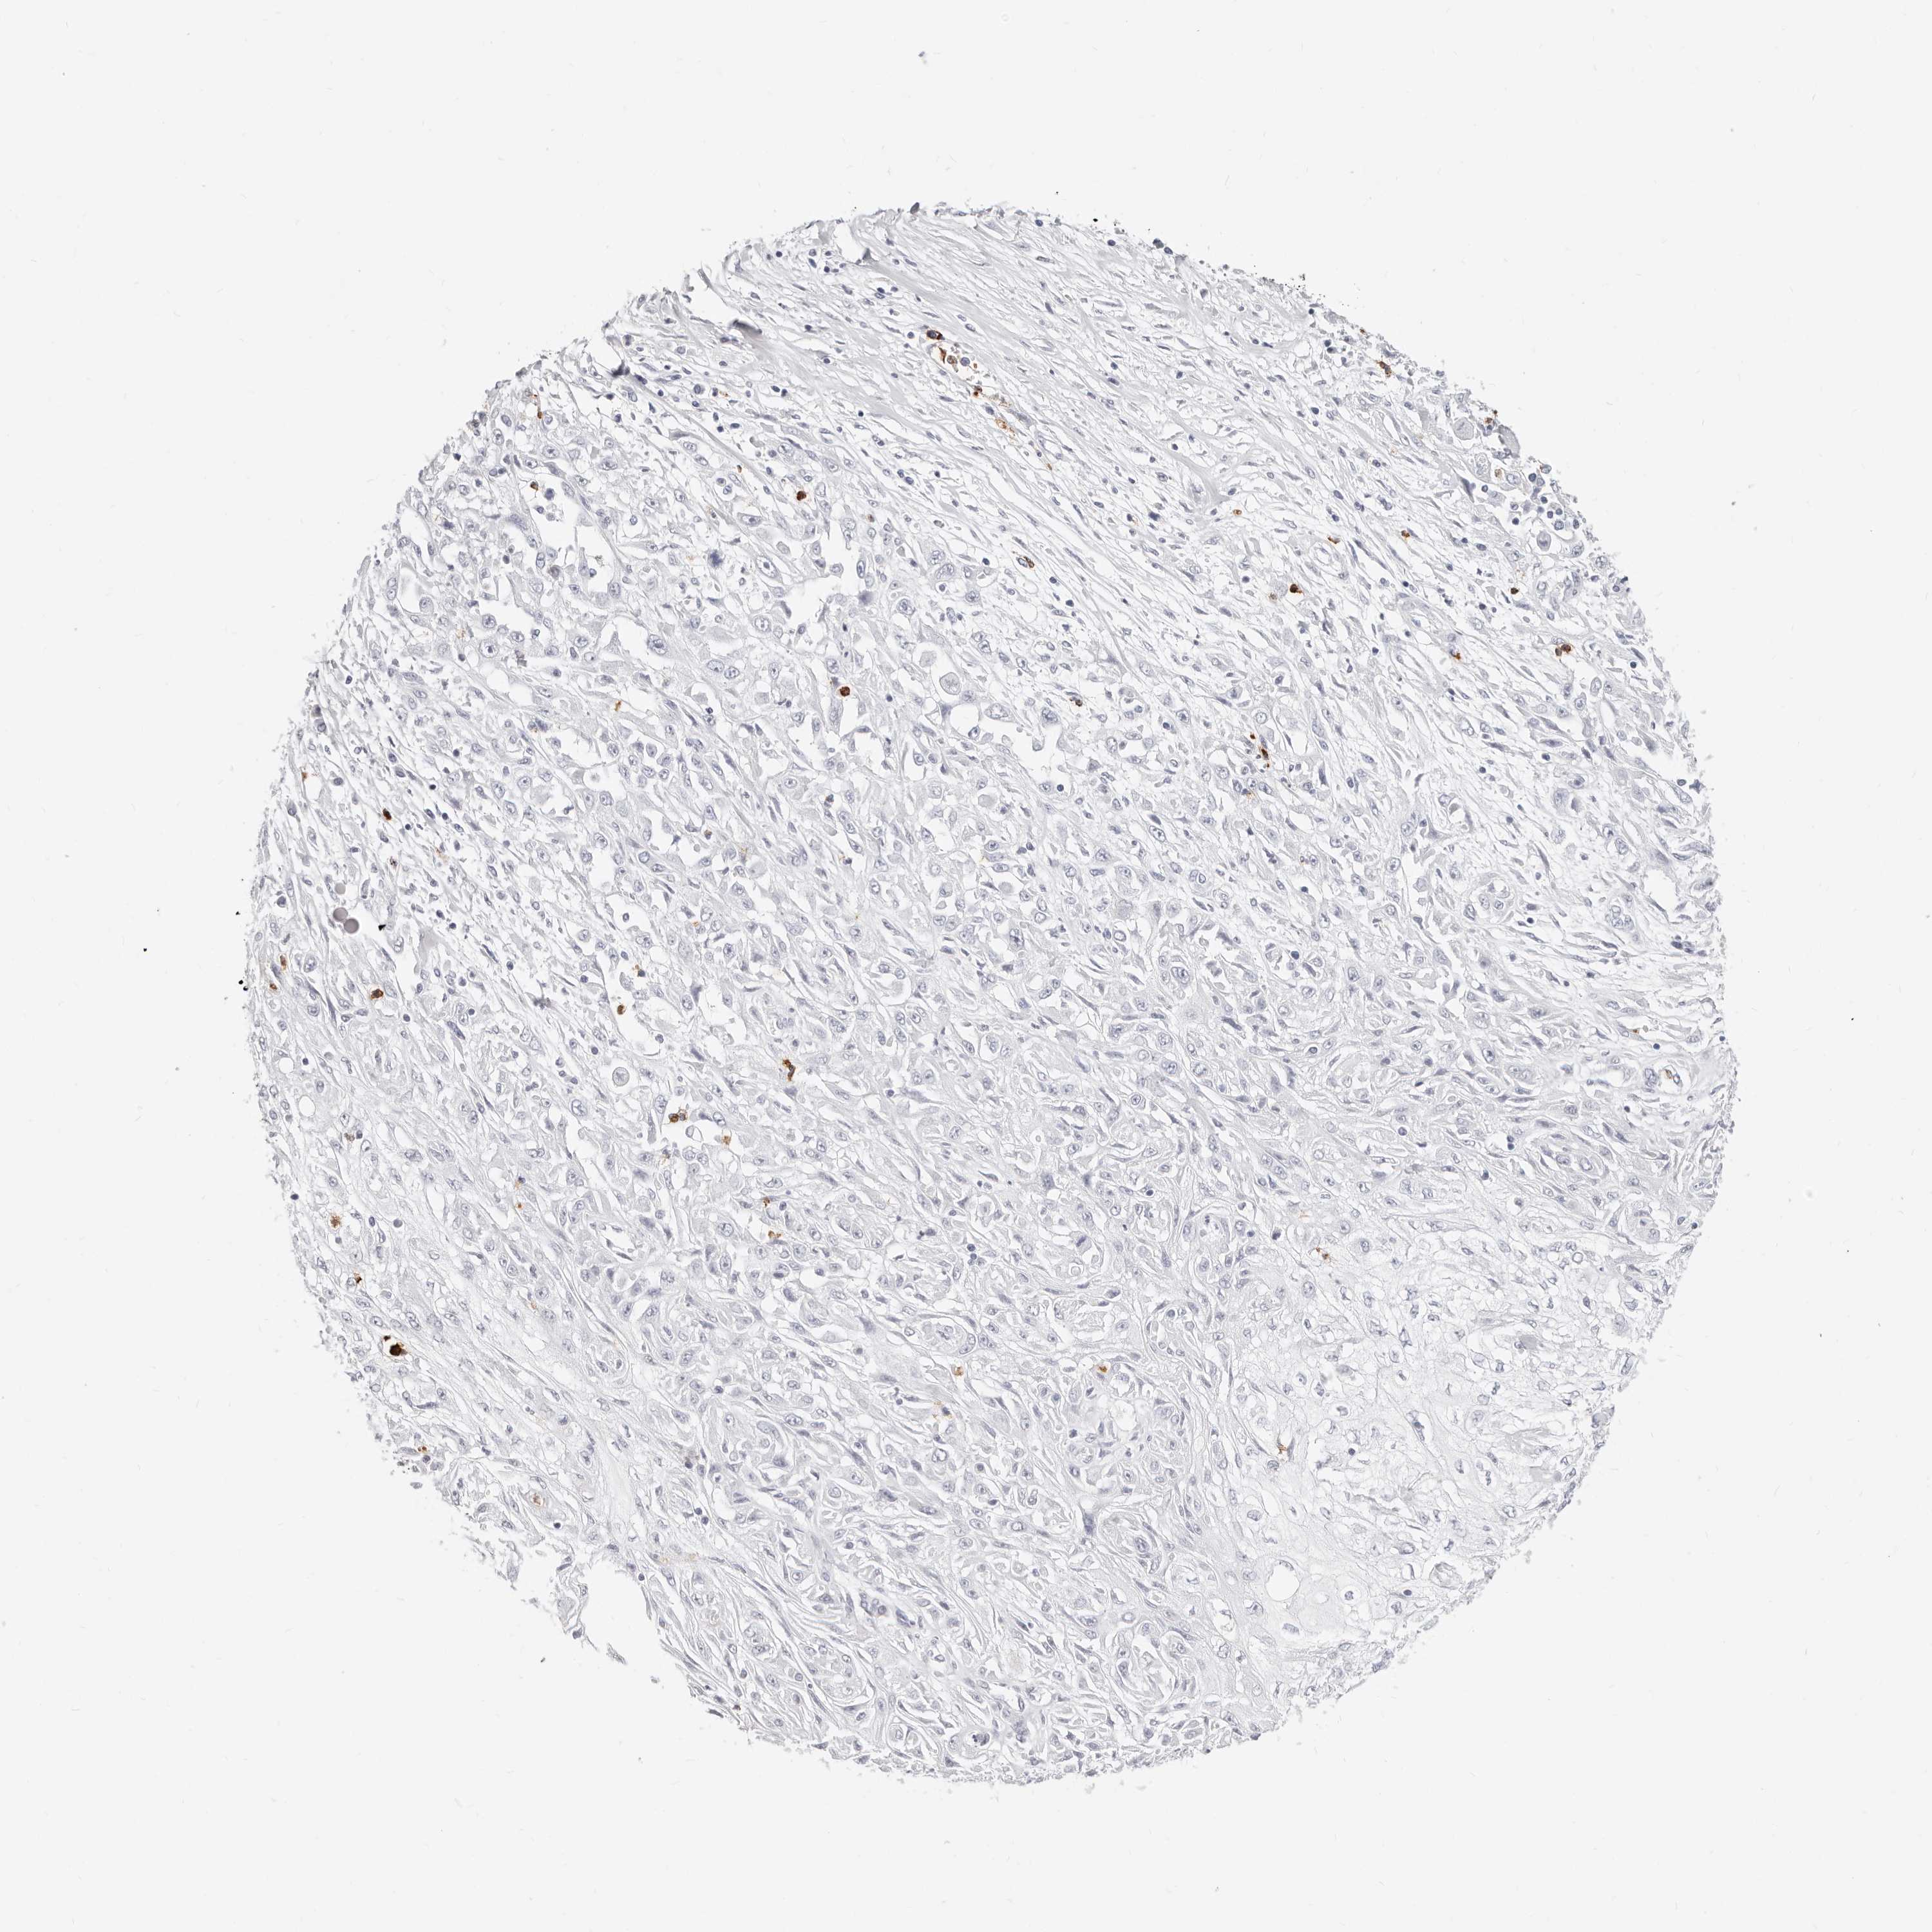

SKIN CANCER - Protein expressioni

A mouse-over function shows sample information and annotation data. Click on an image to view it in a full screen mode. Samples can be filtered based on level of antibody staining by selecting one or several of the following categories: high, medium, low and not detected. The assay and annotation is described here.

Antibody stainingi

Antibody staining in the annotated cell types in the current human tissue is reported as not detected, low, medium, or high, based on conventional immunohistochemistry profiling in selected tissues. This score is based on the combination of the staining intensity and fraction of stained cells.

Each image is clickable and will lead to virtual microscopy that enables deeper exploration of all samples and also displays staining intensity scores, fraction scores and subcellular localization as well as patient and tissue information for each sample.

Antibody CAB016522

Squamous cell carcinoma, metastatic, NOS